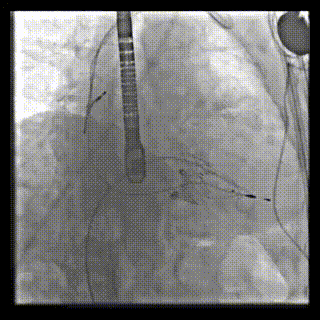

三例患者入院后,葛均波院士團(tuán)隊周達(dá)新教授、潘文志教授、張源博士、陳莎莎博士及心超室的潘翠珍教授、李偉教授對患者的情況進(jìn)行詳細(xì)評估和討論,最終決定為三例患者選擇LuX-Valve Plus40mm、50mm和50mm型號的瓣膜進(jìn)行手術(shù)治療。手術(shù)后即刻拔除氣管插管,術(shù)后患者三尖瓣反流癥狀得到顯著改善,復(fù)查心超結(jié)果顯示人工三尖瓣瓣膜支架固定穩(wěn)定,瓣葉關(guān)閉形態(tài)未見異常,未見明顯反流。